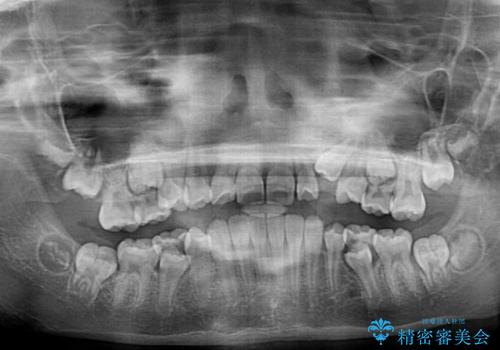

- 小学校での定期歯科検診にて歯列不正を指摘されたとのことで来院された患者様です。

左上の犬歯が低位に埋伏しており、将来八重歯になるリスクが高いと判断されたため、補助装置とワイヤーを用いて犬歯を通常の位置まで移動させることとしました。